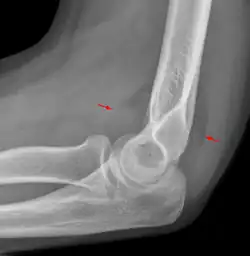

Fat pad sign: Ventral fat pad bowed and dorsal fat pad visible in a case of a nondisplaced fracture of the radius head which is not visible directly.